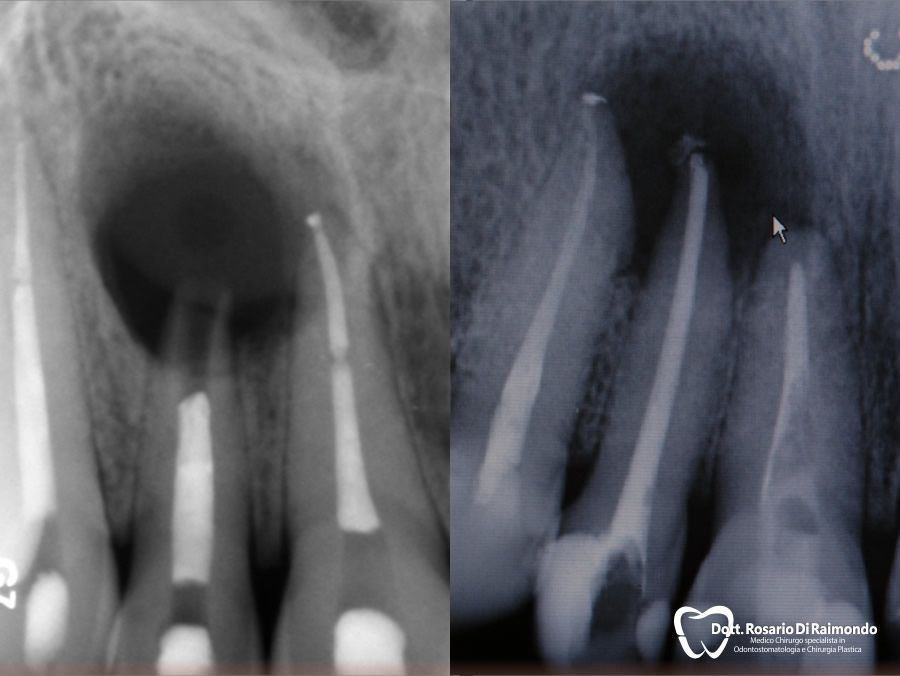

Granulomi

Il granuloma dentale (detto anche granuloma apicale), è una neoformazione infiammatoria cronica a livello dell’apice dei denti di origine batterica e nella maggior parte dei casi è asintomatico, anche se tuttavia può causare la presenza di fistole nella gengiva con fuoriuscita di pus. I granulomi apicali si diagnosticano mediante Rx endorale e il suo trattamento consiste nella terapia canalare (endodonzia del dente o ritrattamento endodontico) e terapia antibiotica.

Apicectomie

L'apicectomia è un piccolo intervento chirurgico rivolto a rimuovere il granuloma apicale nei denti malati in cui la terapia canalare tradizionale non prospetta un risultato predicibile.

In molti casi, la rimozione del granuloma dentale si associa alla asportazione dell'apice radicolare.

L'indicazione più frequente per l'apicectomia è l'insuccesso di una terapia endodontica di un elemento dentario la cui conservazione è ritenuta necessaria.

Casi Trattati

Di seguito riportiamo alcune fotografie di casi esplicativi di Chirurgia Orale.